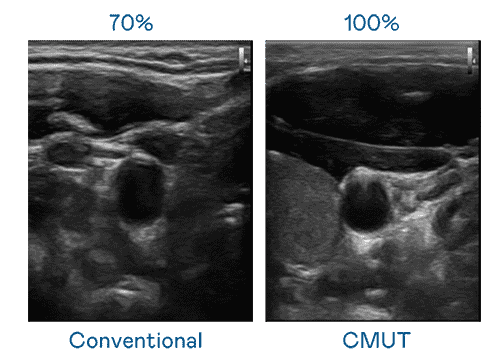

CMUT 技术是一种用电容式微机电元件来产生超音波讯号的技术。。。。与传统 PZT 压电式技术相比,,CMUT 频宽增加 30%,,,更宽频的超音波讯号让影像解析度大幅提升,,是实现高影像品质医疗超音波扫描、、促进精准医疗发展的关键技术。。。。

大频宽带来超清晰影像

超音波影像的解析度高低,,,首先取决于探头能发出的讯号频宽。。。。28国际 CMUT 可提供高清晰的超音波讯号,,提供高频宽、、高灵敏度、、、、影像纹理细节更高的超音波影像,,协助医护人员缩短影像判读时间及利用精准的医疗影像进行诊断。。。